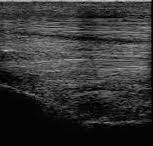

Ultrasonographic evaluation for fiber disruption, echogenicity loss, and periligamentous fibrosis

Visual representation of the SL